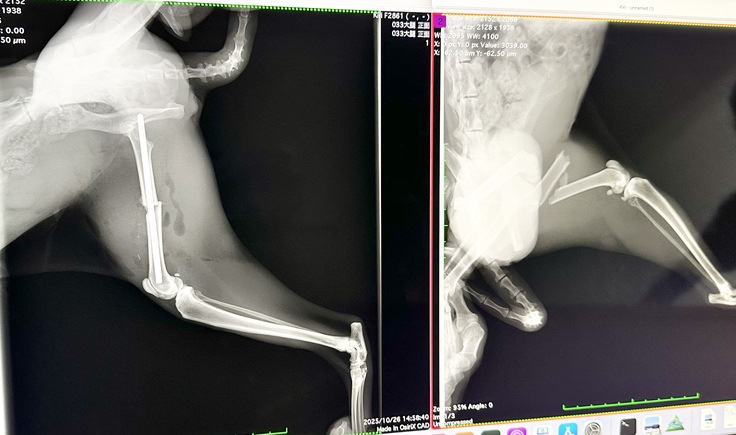

昨日保護した母猫 祥(さち)

本日手術をしていただき、先程面会に行ってきました!!

左足負傷して10日目ですが、骨折端に肉芽が巻き付いて骨が動かないほどガチガチだったそうです。

巻き付いた肉芽を丁寧に剥がしてピンで固定していただきました。

術後1ヶ月はケージ内で安静にしなければなりませんが、骨折の状態次第でフリーにできるそうです。